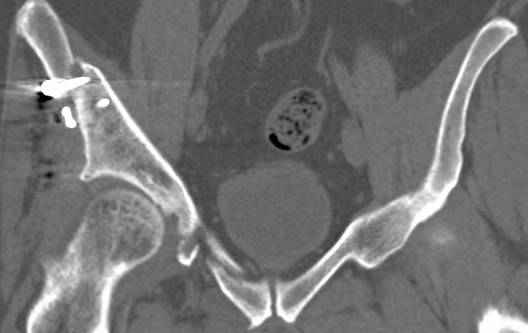

Re: перелом правой половины таза

высылаю дополнительно сканы.